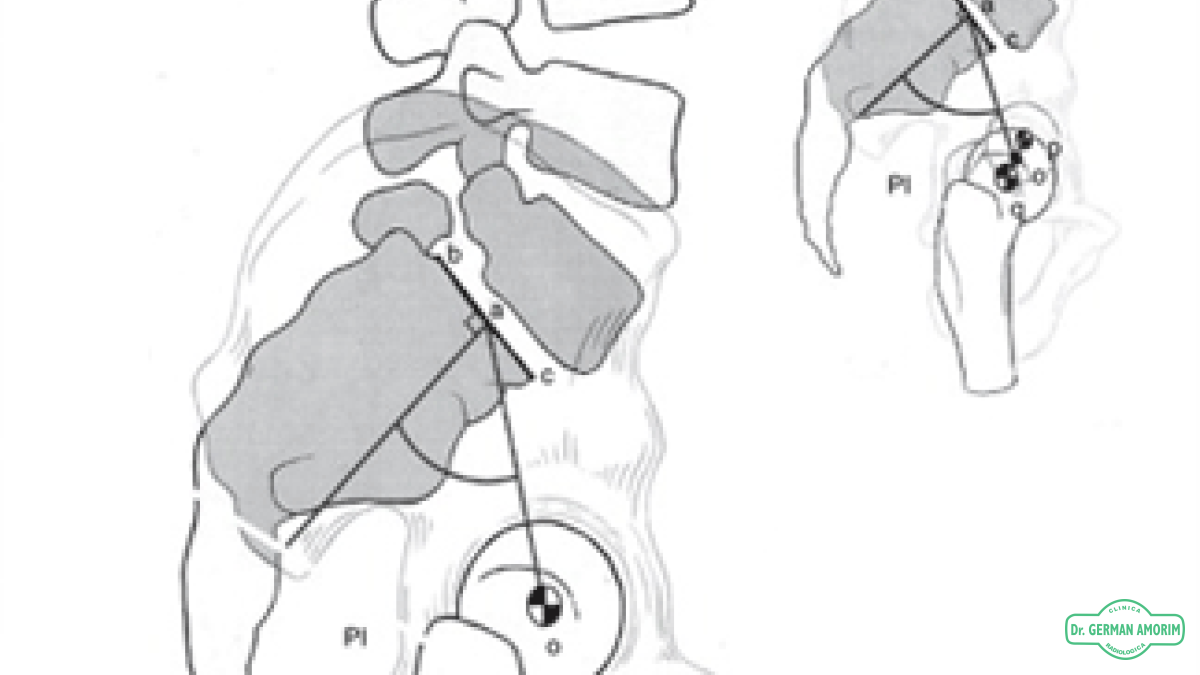

En la visión de frente y en la visión de perfil se controlan las curvaturas que deben ser cervical y lumbar en lordosis (concavidad posterior) y dorsal y lumbar en cifosis (concavidad anterior).

Actualmente se realizan espinogramas digitales que permiten de manera informática medir la alineación y los ángulos de las curvaturas de la columna tanto normales como patológicas.

Esta mediciones múltiples muestra con mayor exactitud los ángulos de Cobb.